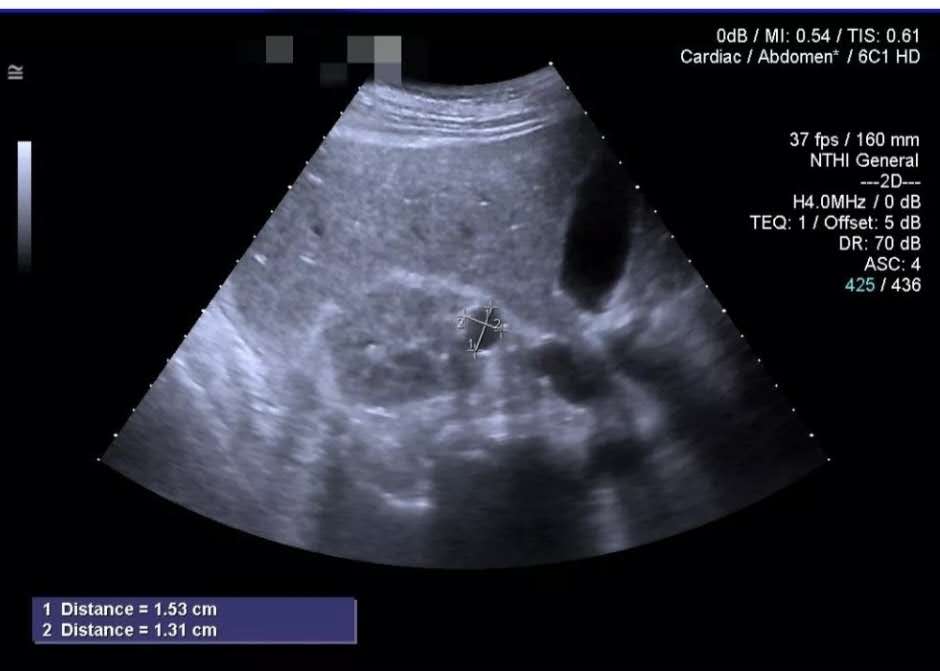

●那么单纯性肾囊肿在B超下是怎么一个特点呢?如下:超声下肾脏内可见单个或多个无回声团块,较大时突像包膜外,壁薄,边界清楚,形态较规则,内部透声好,后方回声增强。如果是新鲜出血时,内部可见实质性稍强回声,时间较长时回声减弱。如果肾囊肿已经出现感染的话,一般会提示囊壁不同程度的增厚,囊内出现细弱点状回声等特点。